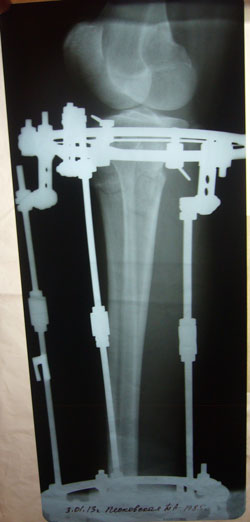

рентгеновские снимки от 03.01.2013г.

2 месяца с момента операции.

P1060108.JPG

P1060107.JPG

P1060106.JPG